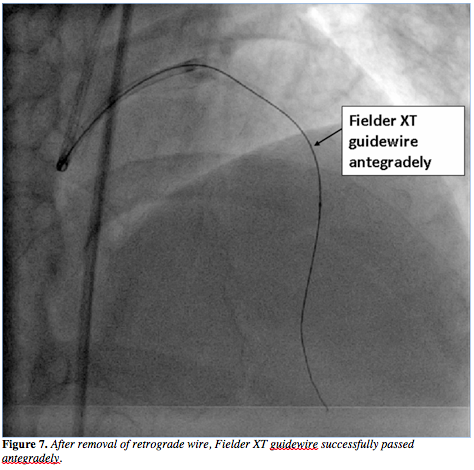

After advancing the wire through the distal septal branch, the wire was navigated into the CTO retrogradely. A 180 cm Corsair hybrid catheter (Asahi Intecc) was loaded over the 300 cm Fielder FC wire in order to make an attempt to advance it retrogradely over the CTO segment (Figure 4). However, because of the hard proximal cap of the CTO segment, the retrograde corsair device had difficulty in getting into the true lumen proximal to the CTO. We then introduced another Fielder XT wire with a 1.2 mm over-the-wire balloon antegradely (Figure 5). The antegrade wire was advanced into the proximal cap subintimally and balloon dilatation at nominal pressure was performed in the subintima. After this, the retrograde wire

was then advanced through the subintimal dissection into the proximal LAD (Figure 6) and then the Corsair was advanced over this wire proximal to the CTO segment. As a result, the true lumen of the distal LAD was then successfully negotiated with a Fielder XT guidewire in an antegrade fashion (Figure 7). The retrograde wire with Corsair was removed. After successful balloon dilatation, two Yukon stents (Translumina) of 2.5 x 32 mm and 2.5 x 28 mm were deployed (Figures 8 and 9), with an optimal angiographic result (Figure 10 and Video 2). The patient is free of symptoms after 6 months of follow-up.